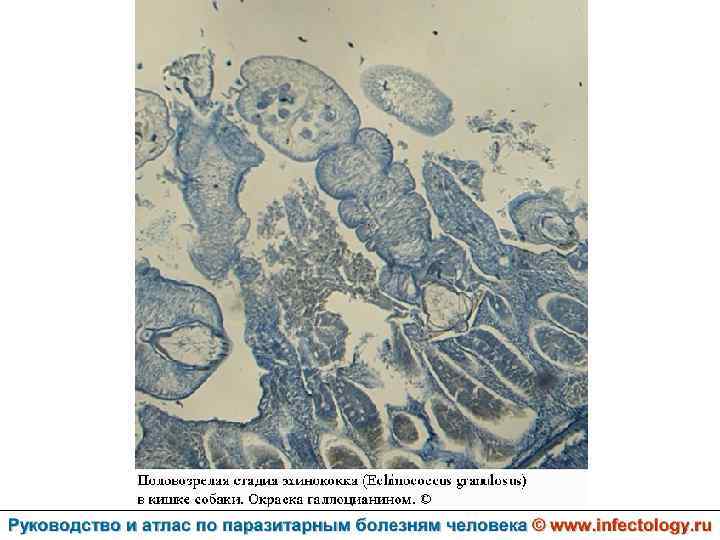

Цистный эхинококкоз (цистный гидатидоз) (шифр по МКБ 10 - B 67. 0 -4) – зоонозный биогельминтоз, характеризующийся хроническим течением, образованием кист и деструктивным поражением печени, легких и других органов.